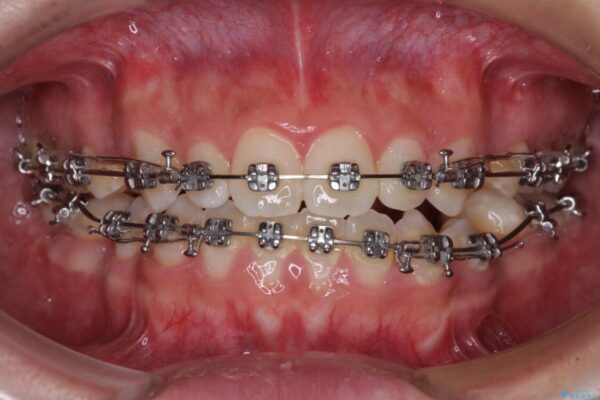

治療途中

• 口元の突出感を改善 受け口傾向の咬み合わせの抜歯矯正 治療途中画像